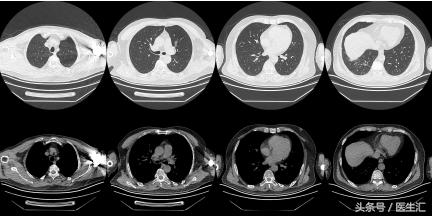

【最终诊断】

肺栓塞

【治疗】

抗凝

治疗后复查胸部CT(2011.11.18)